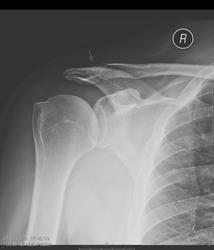

Укладка правильная (оценивается по виду головки плечевой кости)